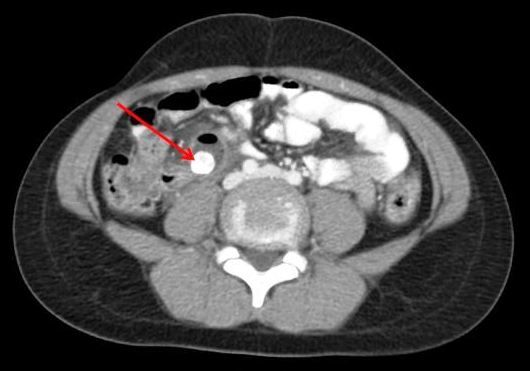

CT scan of the abdomen with contrast showed a 1.1-cm calcified density in the right lower quadrant and an adjacent 1.8 x 1.8-cm fluid collection (Figures 1, 2). The patient underwent exploratory laparotomy the next day and was found to have an appendicolith embedded below the mesentery of the terminal ileum with adjacent abscess; no appendiceal stump was present. A diagnosis of retained appendicolith with abscess formation was made, and the abscess and nidus were removed. The patient rapidly improved without complication and was discharged 1 week following surgery.